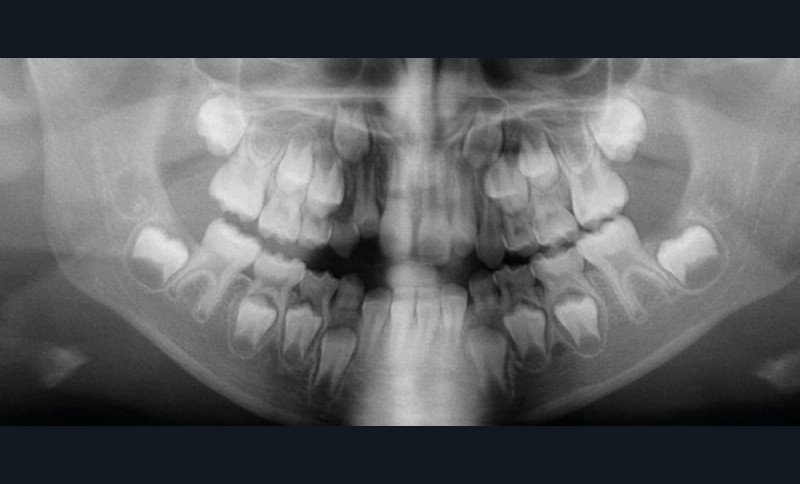

Cette patiente a été suivie dans le cadre d’un traitement interceptif alors qu’elle avait 9 ans. Elle présentait une endognathie maxillaire et une béance antérieure importante liées à des troubles fonctionnels évidents. En effet, l’examen clinique révélait une ventilation buccale exclusive, des ronflements nocturnes et une déglutition atypique. Nous avions noté à l’époque un manque de place pour l’évolution des dents définitives et un inversé d’articulé bilatéral. Les parents avaient rencontré un médecin ORL, mais avaient refusé une intervention visant à enlever les amygdales. Les deux canines maxillaires étaient incluses (fig. 1 à 6).

Quelques années plus tard, au moment de démarrer sa prise en charge orthodontique, la patiente présentait à nouveau une béance antérieure, un décalage des milieux incisifs de 2 mm et le problème transversal avait récidivé. Lors de l’examen clinique, elle présentait un inversé d’occlusion bilatéral postérieur et une ventilation buccale exclusive. À la suite du refus de réaliser l’amygdalectomie de façon précoce, elle ronflait toujours et sa déglutition ne s’était pas modifiée malgré des séances d’orthophonie (fig. 7 à 15).